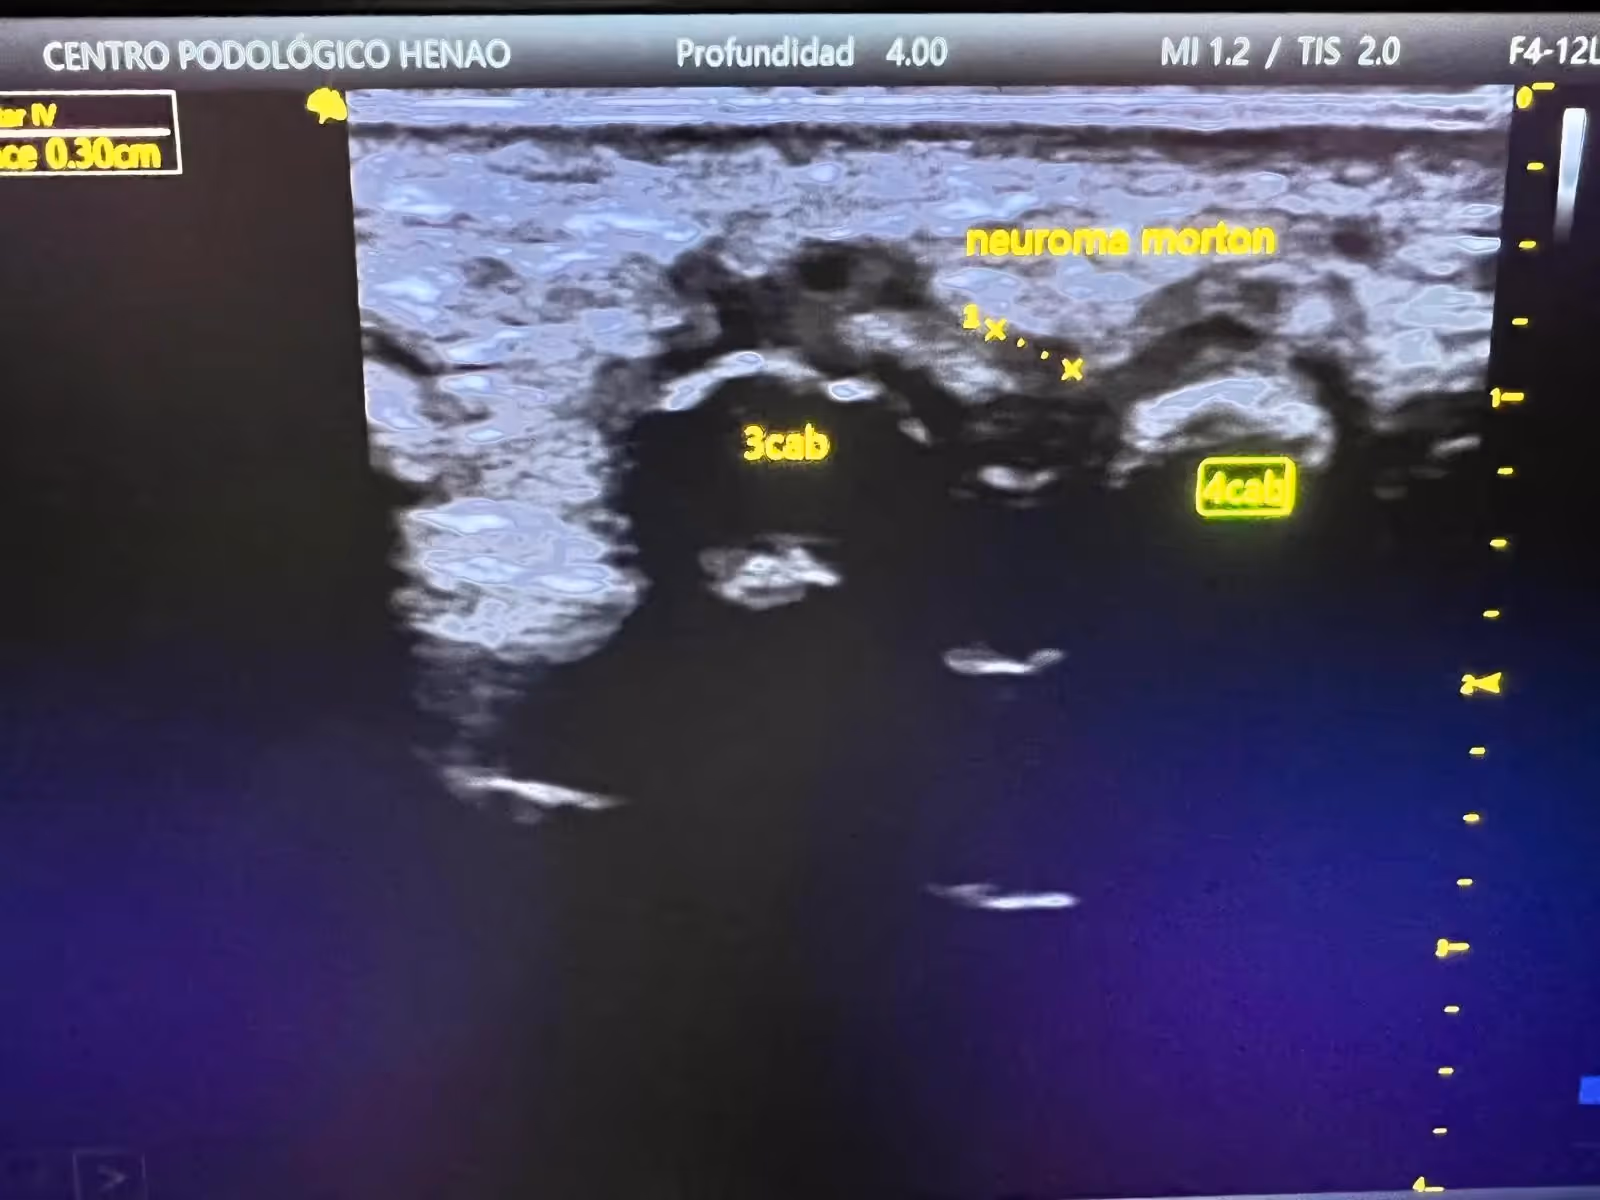

Ecografía de Alta Resolución: En nuestro centro utilizamos ecografía especializada que nos permite:

- Visualización directa del neuroma: Medición precisa del engrosamiento nervioso

- Evaluación en tiempo real: Observación del comportamiento del nervio durante el movimiento

- Diagnóstico diferencial: Exclusión de otras patologías (bursitis, quistes)

- Seguimiento de la evolución: Monitorización de la respuesta al tratamiento

Características Ecográficas del Neuroma:

- Imagen hipoecogénica (oscura) fusiforme

- Tamaño típicamente >5mm en el eje transversal

- Localización en el espacio intermetatarsal

- Ausencia de vascularización en Doppler